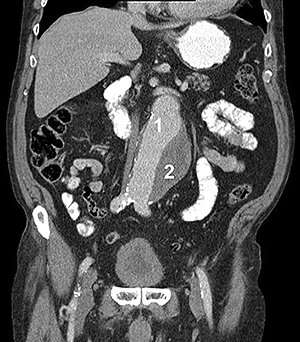

аневризма аорти

Рисунок 2. Комп'ютерна томографія:

1 - зона вільного кровотоку,

2 - тромбована частина аневризми

- ангіографія: дає змогу виявити деформацію аорти та її гілок, однак справжні розміри аневризми не завжди видно у зв'язку з можливою наявністю пристінкового тромбозу порожнини аневризми (рис. 2).

- комп'ютерна томографія (КТ) з контрастним посиленням: дає змогу точно виявити межі та форму аневризми й незмінених відділів аорти, обчислити розміри аорти та прилеглих артерій, оцінити ступінь їхньої звивистості. Одна з найбільш інформативних діагностичних методик, абсолютно необхідна для правильного підбору стент-графту.